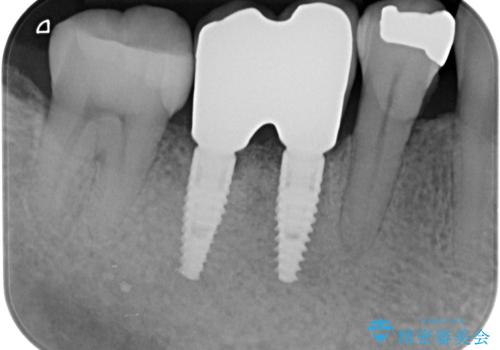

無事インプラントが入りました。

インプラント治療をしてもメンテナンスを怠っているとインプラント歯周炎になるリスクがあがるのでメンテナンスをお勧めします。